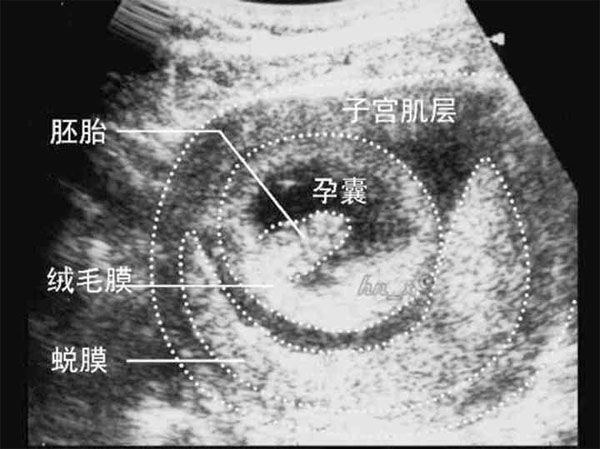

到底肚子里的宝宝是男孩还是女孩,这是很多准爸爸和准妈妈都很关心的问题,民间也有很多预测性别的方法,不过相对于流传的生男生女计算公式,其实通过B超检查后,观察孕囊形状来判断性别的方法更为科学。

想要知道自己怀的是男孩还是女孩,可以通过阴道B超检查之后,观察孕囊形状判断男女,不过不是简单地看B超单上的形状,而是根据孕囊的三边数据去想象它的形状。

看孕囊形状必须要是8周之前的阴道B超,而且有孕囊的三个数据,同时三个数据都要有十分的精确值,这样才能提升预测生男生女的成功率。

必须是8周之前阴道B超,单孕囊要看早期形状,40-50天左右是最准的,如果是9周以后的数据准确性就会很低,而如果是腹超,也会降低准确率。

需要有孕囊的3个边长数据,3个数据中,最长径13~18毫米,这个尺寸不是绝对的,只是尺寸距离这个区间越大,判断准确率就越低。

孕囊的3三个数据,有两个数据基本相等,另一个数据是前两个数据的一半,那么是男孩,如果三个数据接近等差数列,或者另一个数据是前两个近似数据数据的0.7~2.6倍,那有可能就是女孩。